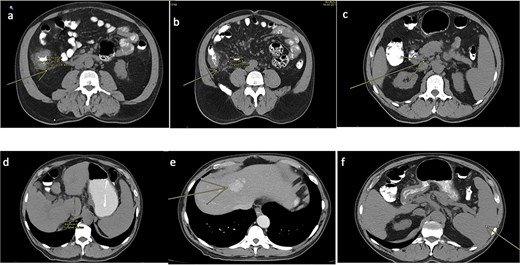

A 77-year-old male with a medical history of right-sided colon cancer was diagnosed by colonoscopy, which revealed an obstructive tumor at the level of the cecum. An abdominal and pelvic computed tomography (CT) scan demonstrated a circumferential and irregular thickening consistent with a tumor in the cecum, associated with pericolic fat stranding, retroperitoneal lymphadenopathy, altered mesenteric fat, signs of chronic liver disease, a hepatic hemangioma, splenomegaly, and features of portal hypertension (Fig. 1).

CT scan of the abdomen and pelvis (non-contrast). (a) Tumoral concentric thickening of the cecum with pericolic and mesenteric fat stranding. (b) Infiltrative-appearing lymphadenopathy adjacent to the tumor. (c) Retroperitoneal lymphadenopathy. (d) Signs of chronic liver disease and portal hypertension. (e) Hepatic hemangioma. (f) Splenomegaly.